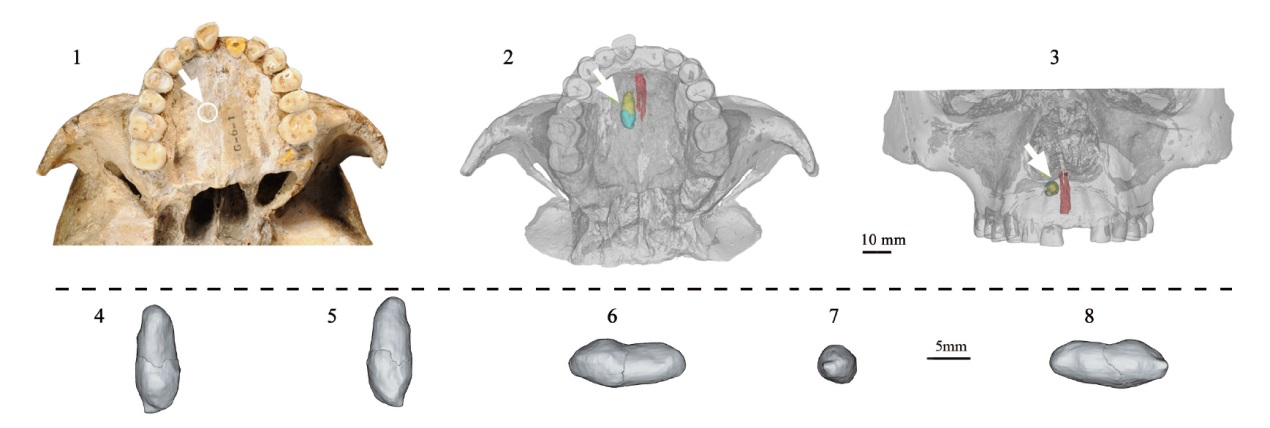

图2 柳江人上颌区域 1.上颌区域底面观Bottom view of the Liujiang maxillary region; 2. 上颌区域三维重建底面观,多生齿的齿冠和齿根分别以蓝色和黄色表示,红色为鼻腭管Bottom view of the virtual reconstruction of the Liujiang maxillary region, the crown and root of the Liujiang supernumerary tooth are shown in blue and yellow, respectively, the nasopalatine canal is shown in red; 3. 上颌区域三维重建正面观,多生齿的齿冠和齿根分别以蓝色和黄色表示,红色为鼻腭管Frontal view of the virtual reconstruction of the maxillary region, the crown and root of the Liujiang supernumerary tooth are shown in blue and yellow, respectively, the nasopalatine canal is shown in red; 4. 顶面观Top view; 5. 底面观Bottom view; 6. 外侧观Lateral view; 7. 后面观Posterior view; 8. 内侧观Medial view; 白色箭头指示多生齿The white arrows indicate the supernumerary tooth.

Fig.2 The maxillary region of Liujiang